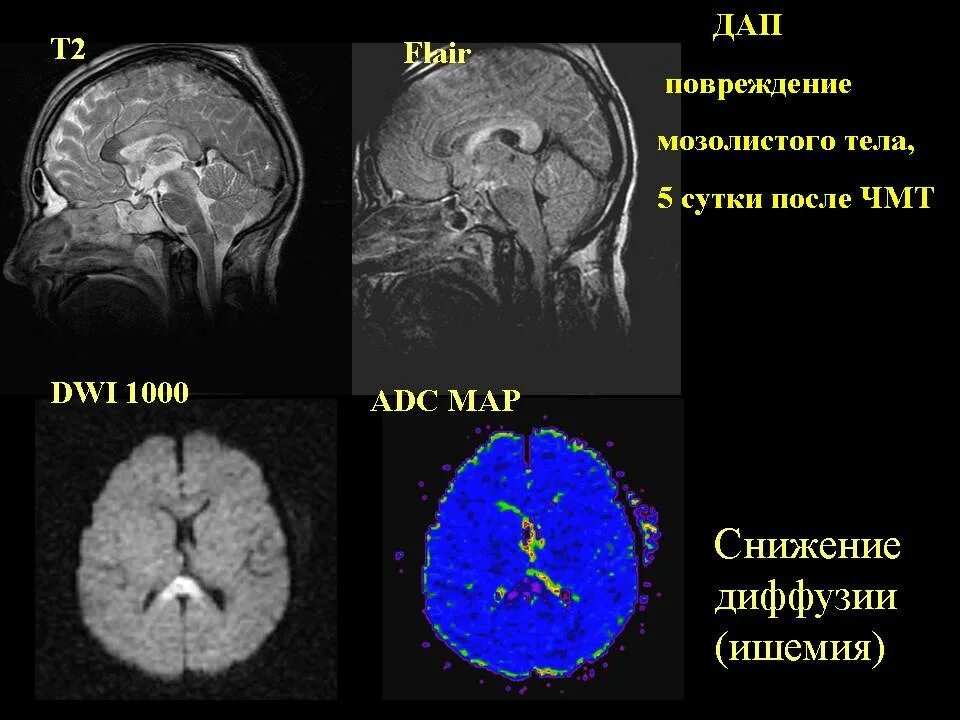

Диффузное аксональное повреждение